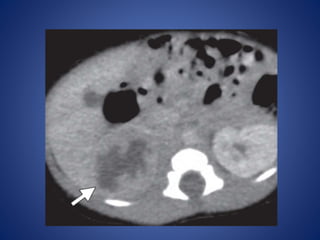

At CT, the solid component of juvenile GCT may show iso- to hyperattenuation

as well as contrast enhancement.

Hyperattenuating hemorrhage within cystic components of the mass is a

characteristic finding. Calcifications are not a feature of juvenile GCT.

At CT, thesolid component of juvenile GCT may show iso- to hyperattenuation as well as contrast enhancement. Hyperattenuating hemorrhage within cystic components of the mass is a characteristic finding. Calcifications are not a feature of juvenile GCT.